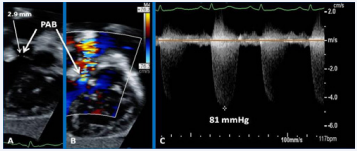

Figure 21 Selected echocardiographic video frames demonstrating pulmonary artery band (PAB) with narrow diameter of 2.9 mm by 2D (A) and by color flow (B) and a high gradient (81 mmHg) by continuous wave Doppler (C) are shown [69].

Echocardiographic and angiographic examples of some of the banding procedure are shown in Figures 21 to 23.